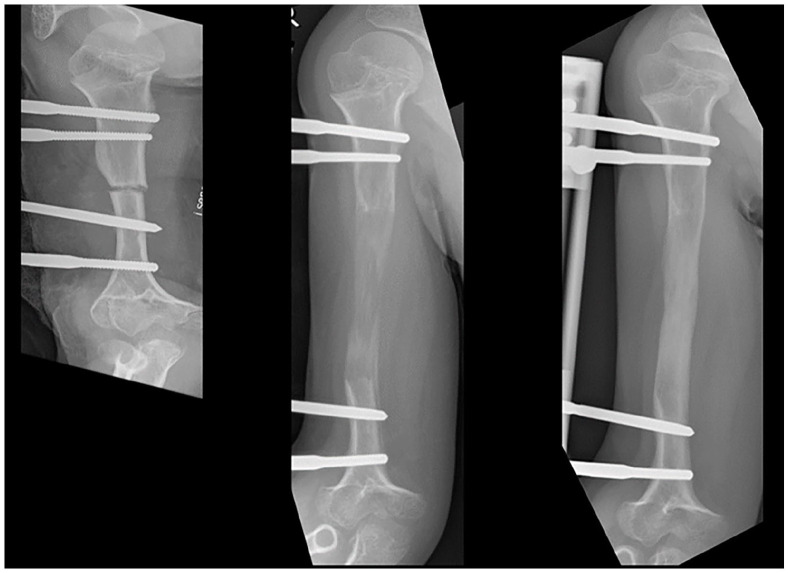

软骨发育不全症是一种最常见的遗传性矮小,是由成纤维细胞生长因子受体 3 基因突变引起的。软骨发育不全症的典型临床特征包括身材矮小、根茎发育不全、关节过度松弛、脊柱畸形和上下肢畸形。后者是最先进的矫形治疗方案所面临的挑战之一,并极大地加重了软骨发育不全患者的疾病负担。在手术干预方面,应考虑多学科术前个体决策。目前已开发出治疗软骨发育不全的新药物,其中一些已在多个国家获准用于临床。虽然有关软骨发育不全的研究文章数量正在迅速增加,但仍有许多未知或有争议的矫形课题。此外,鉴于新的医学发展对生长和潜在的其他影响有所改善,矫形治疗(如引导生长、肢体延长和畸形矫正)的时机和算法需要重新评估。虽然站立高度是医学治疗的主要研究重点,但全面评估这种多因素疾病的矫形参数也至关重要。目前对软骨发育不全患者的治疗需要专门的多学科中心提供过渡性护理和个体矫形咨询。

Achondroplasia, the most common form of inherited disproportionate short stature, is caused by mutations in the fibroblast growth factor receptor 3 gene. The typical clinical features of achondroplasia include short stature, rhizomelic disproportion, joint hyperlaxity, spinal deformity and deformity of the upper and lower limbs. The latter are among the challenges of state-of-the-art orthopaedic treatment plans and significantly contribute to the burden of the disease in individuals with achondroplasia. Multidisciplinary preoperative individual decision-making concerning surgical interventions should be considered. New medical treatments for achondroplasia have been developed and (some) have been approved for clinical use in several countries. While the number of research articles on achondroplasia is increasing rapidly, many unknown or controversial orthopaedic topics remain. Furthermore, in view of new medical developments with improvements in growth and potentially other effects, the timing and algorithms of orthopaedic treatments (e.g. guided growth, limb lengthening and deformity correction) need to be re-evaluated. While standing height is the primary research focus in medical therapy, it is crucial to comprehensively assess orthopaedic parameters in this multifactorial disease. The current treatment of patients with achondroplasia requires specialised multidisciplinary centres with transitional care and individual orthopaedic counselling.